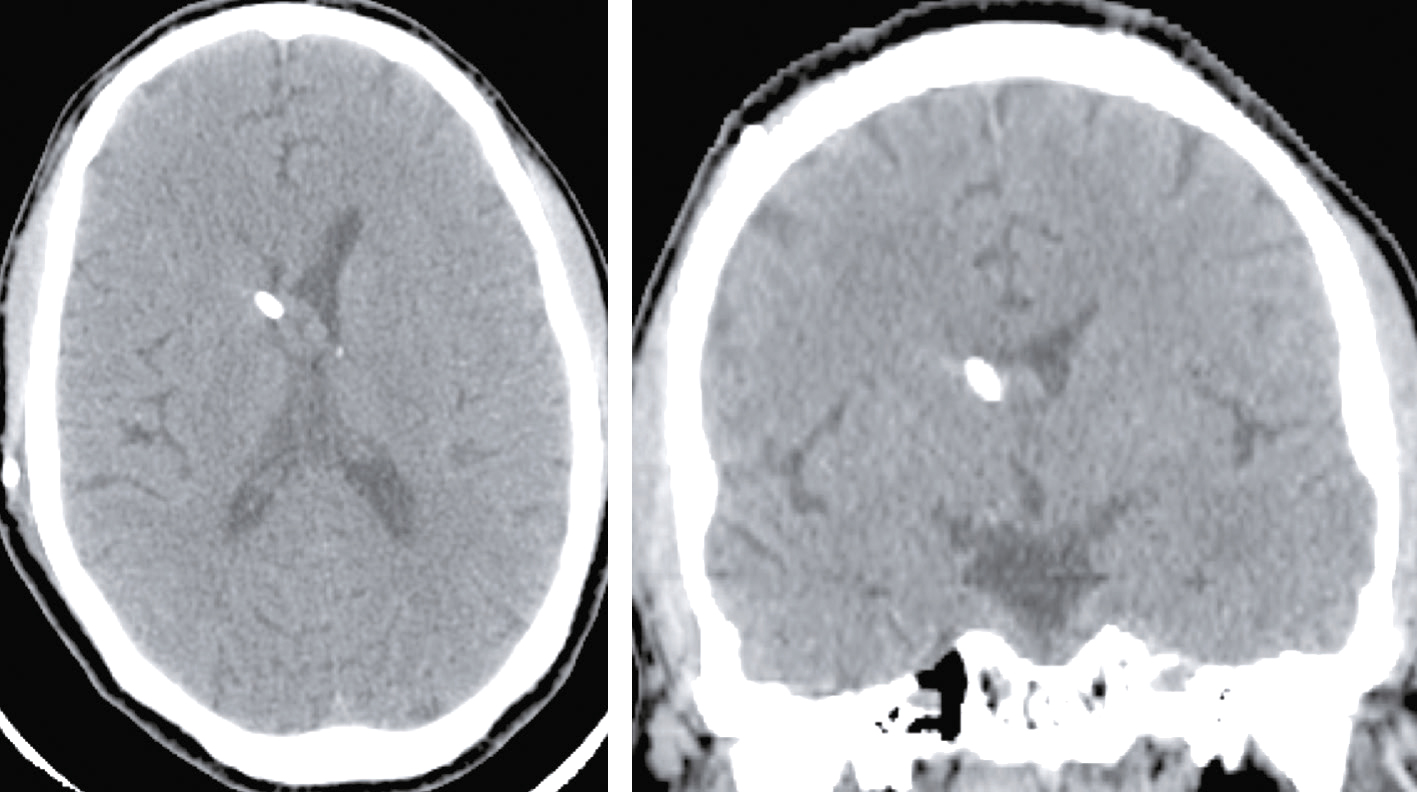

Une nouvelle IRM cérébrale est réalisée devant cette diplopie. Décrivez le cliché (fig. 31.1).

L'image montre une coupe transversale d'un cerveau humain obtenue par imagerie par résonance magnétique (IRM). Cette image est une vue axiale, ce qui signifie qu'elle est prise horizontalement à travers le cerveau. On peut observer les différentes structures cérébrales, y compris la matière grise et la matière blanche. Les ventricules latéraux, qui sont des cavités remplies de liquide céphalo-rachidien, sont visibles au centre de l'image. Les zones plus claires autour des ventricules peuvent indiquer des anomalies ou des lésions, souvent associées à des conditions neurologiques comme la sclérose en plaques. Les contours du cerveau sont bien définis, et les différentes régions du cortex cérébral sont clairement visibles. Cette image est intéressante car elle permet aux médecins de diagnostiquer et de surveiller diverses maladies neurologiques en visualisant les structures internes du cerveau avec une grande précision. L'IRM est une technique non invasive qui utilise des champs magnétiques et des ondes radio pour produire des images détaillées des organes et des tissus internes, ce qui est crucial pour la détection précoce et le traitement des maladies cérébrales.

- A coupe sagittale

- B séquence T1

- C hypersignaux de la substance blanche périventricu-laire

- D hypersignaux du tronc cérébral

- E hypersignaux juxtacorticaux